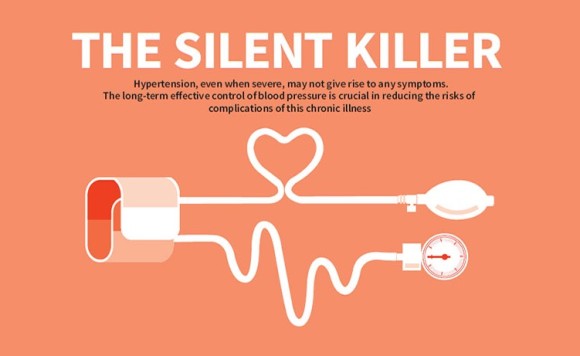

고혈압증 유명한 무언의 살인자?침묵의 살인자

갑자기 겁이 나서 고혈압에 대해 유튜브, 블로그 등 자료를 뒤지기 시작했다.

고혈압이 발생하는 이유는 여러 가지가 있지만 동맥경화(혈관이 좁아지는 현상)를 동반하면 뇌경색, 뇌졸중이 발생해 몸에 마비까지 오고 심하면 죽을 수도 있다고 한다.

또 이런 고혈압은 결국 혈액을 전신으로 보내는 심장에 많은 부하를 줘 심부전증이 발현될 수 있다는 것.

혈압은 나이가 들수록 자연스럽게 올라가게 돼 있다.나이가 들수록 위험해.자기 나이 평균 혈압보다 높은 혈압을 가지고 있다면 고혈압